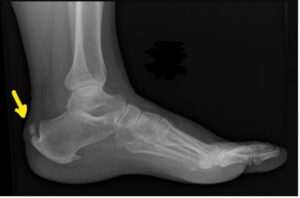

A deformidade de Haglund é um aumento ósseo anormal na região posterossuperior do calcâneo, onde o tendão do calcâneo se insere. Essa protuberância pode ser facilmente visualizada (ver Figura 1) e palpável durante o exame físico.

Radiografias simples e ressonância magnética podem confirmar anormalidades ósseas, mas a correlação com detalhes ultrassonográficos dos tecidos moles corrobora o diagnóstico. Outras causas de dor no calcanhar incluem bursite retrocalcânea/superficial isolada, artropatias sistêmicas e ruptura do tendão calcâneo.